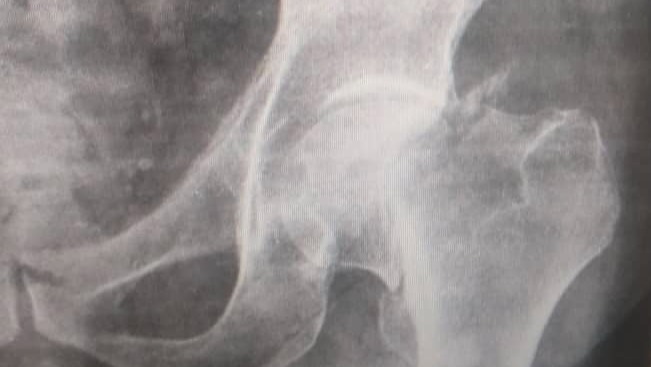

He recently lost balance and fell down on the floor, injuring his left leg. As you can see in the posted x-rays images below, as a result of this accident, he got a femoral neck fracture, which requires surgery to do a partial hip replacement, which includes a prosthetic femur neck and head (Thompson prothesis), besides miscellaneous medical bills and rehabilitation. The estimated cost of the whole procedure will go up to $10,000.